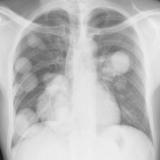

Nodules & Masses

Album: Nodules & Masses

Date: 01/25/2006

Size: 37 items

Views: 60060